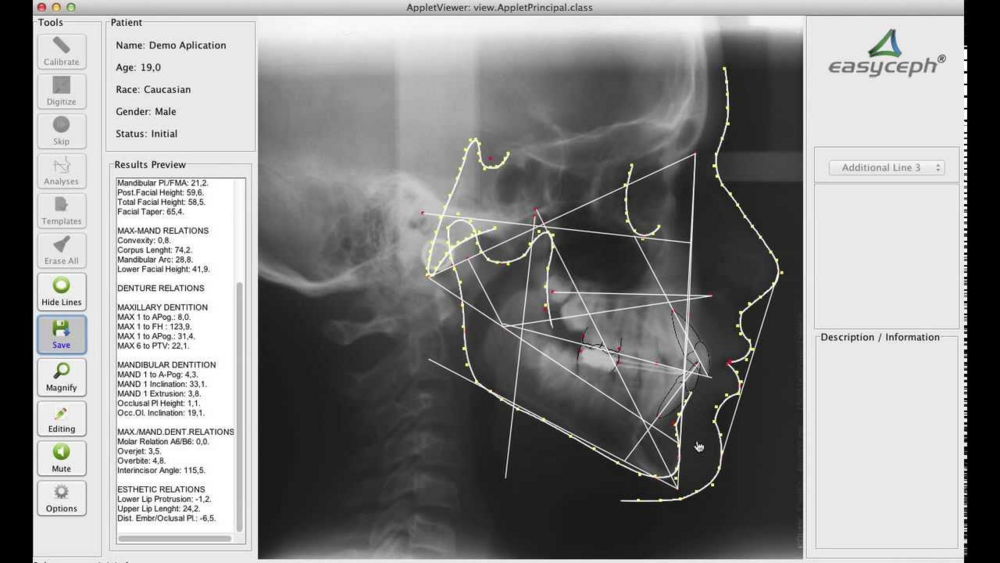

How does one measure the face, each measurement is different . As u know I had masseter muscle detachment so want to workout the distance between the gonial and the widest part of masseter.